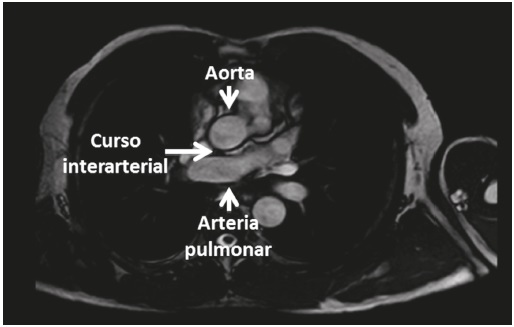

Dado el hallazgo angiográfico se decidió hacer una evaluación anatómica con resonancia magnética cardíaca (RMC) para definir el trayecto de la arteria coronaria izquierda, la severidad de la hipertrofia ventricular izquierda y detectar posibles anomalías concomitantes. La RMC demostró hipertrofia ventricular izquierda posiblemente secundaria a la cardiopatía hipertensiva, origen anómalo de la arteria coronaria izquierda en el seno coronariano derecho, confirmando el hallazgo angiográfico, con trayecto interarterial, entre la aorta y la arteria pulmonar (Figura 4).